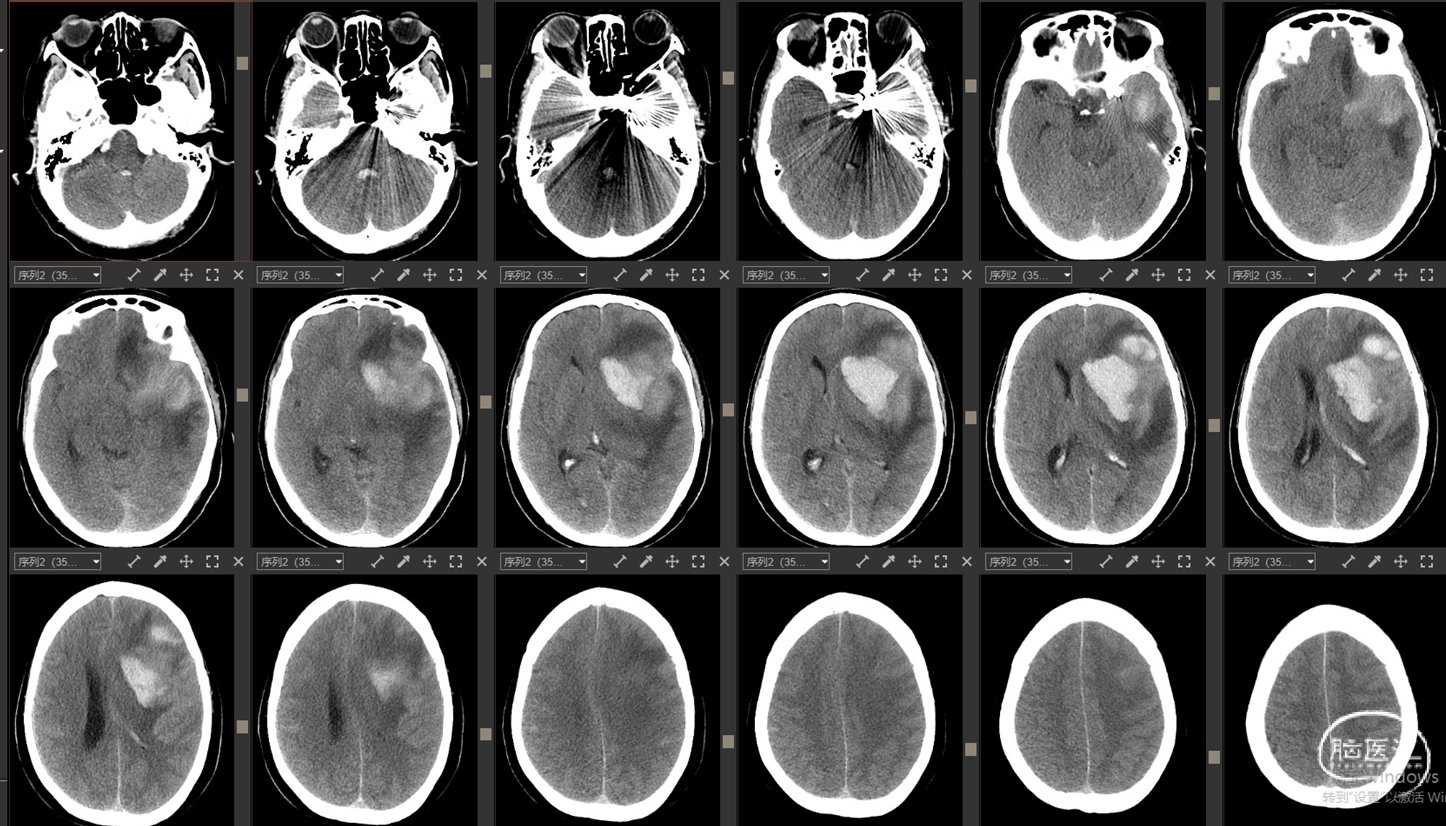

现病史:12小时前无明显诱因突发出现右侧肢体无力,伴言语不能,伴呕吐胃内容物3次,无人事不省,无肢体抽搐,无发热等。就诊当地医院,急查头颅CT示:“颅内出血”,予对症处理后转诊我院。我院急诊查头颅CTA示:“左侧基底节区及左侧额颞叶血肿伴大脑镰下疝、颞叶钩回疝及海马旁回疝可能,左侧颈内动脉C4段所见,考虑多发动脉瘤伴血管畸形,建议DSA检查”。

影像资料:CT、CTA

1.左侧基底节区及左侧额颞叶血肿 2.左侧颈内动脉C4段多发动脉瘤 3.左侧额颞叶血管动静脉畸形

1. 左侧基底节区及左侧额颞叶血肿

2. 左侧颈内动脉C4段动脉瘤破裂致颈内动脉海绵窦瘘

3. 左侧额颞叶血管动静脉畸形?

1. 左侧基底节区及左侧额颞叶血肿

2. 左侧颈内C4段动脉瘤破裂致颈内动脉海绵窦瘘(Barrow A型)

精确诊断:左侧颈内C4段动脉瘤破裂至大脑中浅静脉致左侧基底节区及左侧额颞叶静脉性梗死并出血转化。